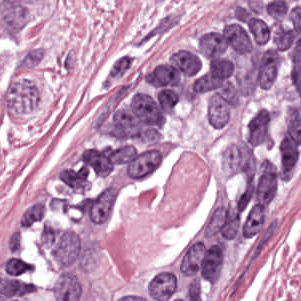

As an essential part of digital pathology, histopathology image analysis is playing increasingly important role in cancer diagnosis, which can provide direct and reliable evidence to diagnose the grade and type of cancer. This paper deals with nuclei segmentation, an important step in histopathological image analysis. The purpose of nuclei semgentation is not only counting the number of nuclei but also obtaining the detailed information of each nucleus. So unlike nuclei detection, here the outputs are the contour of each nucleus instead of only the position of their central points. Hence we can exactly extract each nucleus from the image and make it available for further analysis. For example, the features of the individual nucleus and the distribution of nuclei clusters can be used to grade and classify status of breast cancers [3, 4]. Because of appearance variation such as color, shape, and texture, nuclei segmentation from histopathological images could be very challenging, as illustrated in Fig.1, in which it is very challenging even for human to recognize and segment all nuclei within the images. Fig.1(a) and Fig.1(b) illustrate two histopathological images from different organs. Fig.1(c) and Fig.1(d) are two histopathological images from same organ but have different cancer grade.

H&E stain is the most widely used stain protocol in medical diagnosis. Typically, the nuclei of cells are stained to blue by Haematoxylin while cytoplasm is colored to pink by Eosin. But in practice, the color of H&E stained images could vary a lot due to variation in the H&E reagents, staining process, scanner and the specialist who performs the staining, as shown in Fig.1. A few H&E stain normalization methods[23, 24, 25] have been proposed to eliminate the negative interference caused by color variation. We tried two of them[23, 25] to normalize the raw H&E stained images. For our segmentation algorithm, we did not find any considerable difference between these two normalization methods. Particularly, the result shown in experiment section III is generated based on the images normalized by the method in [23]. Given a target image, this method is able to convert one image’s color into the target image’s color space based on sparse non-negative matrix factorization(NMF). We choose one best stained H&E image as the target and convert other images into its color space. According to the recommendation in [23], the hyper-parameter should be set between 0.01 and 0.1. In our experiment, is set to 0.1.

Figure 6 shows how our method segments the nuclei step by step. The color variety is well controlled by the color normalization procedure. The prediction result shows clear nuclear areas and nucleus boundaries. In the final segmentation result and ground truth image, each nucleus is represented by a different color.